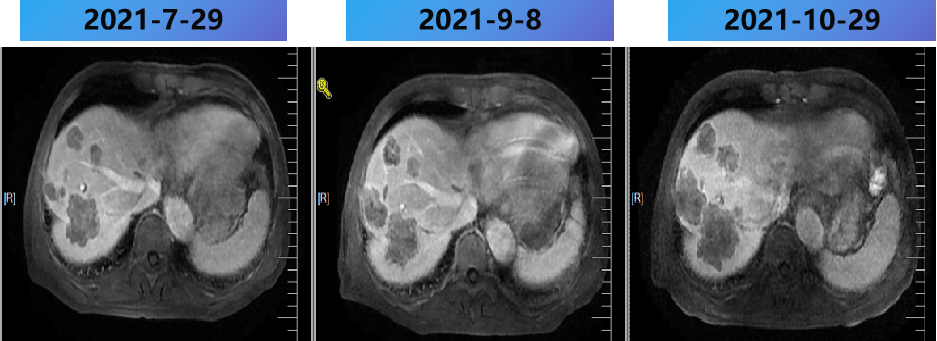

2020-7-5 复查腹部MRI示:乙状结肠癌伴肝转移治疗后改变,对比2020-6-18 MRI,肝内治疗灶凝固坏死显著,肝内未见明显癌灶征象,部分周边反应性改变可能,建议3个月后随诊复查。

(2020-09-12 本院)行磁共振(腹部)检查提示:1.乙状结肠癌伴肝转移治疗后改变,与2020-07-15 MRI片比较,肝内病变凝固坏死灶显著,较前范围减小,肝内未见明确癌灶征象,建议定期随诊观察。2.左肾小囊肿。3.腹腔少许积液。

2021-2-20 (术后8m) 当地复查腹部MRI:肝脏多发转移瘤消融术后,较2021-1-5病变数目增多,体积增大。